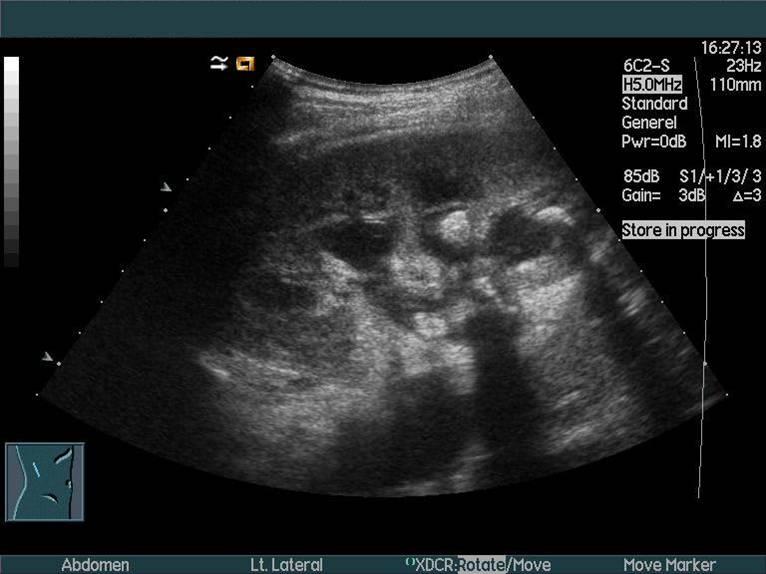

Nyre med pyonefrose (betændelse) påvist med ultralydskanning. Der ses også sten, som giver de sorte slagskygger på billedet. Calyces er dilaterede (de sorte hulrum).